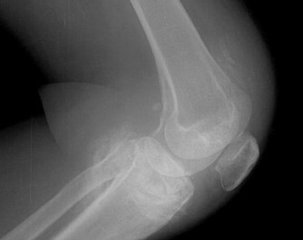

滑膜炎的患者朋友们除了疼痛之外一个最典型的表现就是由滑膜炎引起的膝关节水肿,这是因为患者的关节内有渗出积液造成的,患者的主要表现就是膝关节充血肿胀,疼痛,渗出增多,关节积液,活动下蹲困难,功能受限等等,如果长期得不到 治疗就会形成慢性膝盖滑膜炎,会给患者造成更大的痛苦,那么滑膜炎引发膝关节水肿怎么办?下面郑州痛风风湿病医院专家为您详细讲解。